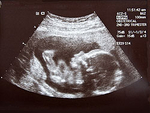

Шевеление плода: когда, как и почему

Считается, что женщина, вынашивающая первенца, начинает ощущать шевеления плода, начиная со срока 20 недель.

Женщины, уже испытавшие радость материнства, как правило, чувствуют первые движения плода раньше - с 18 недель. Те же данные учитываются и при установлении срока беременности по первому шевелению плода.

Однако сроки эти являются примерными, и нормой будет считаться как ощущение шевеления плода на сроке 16 недель, так и в 24 недели. Но действительно ли эти движения плода - первые?